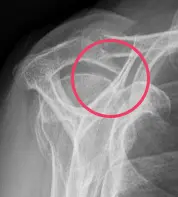

Abbildung: Subacromiales Impingement durch knöchernen Sporn

- Anatomische Enge (z. B. hakenförmiges Acromion, Knochensporne, die den Subacromialraum einengen, Kalkschulter, welche durch die Entzündung des Gewebes zu einer rel. Enge führen)